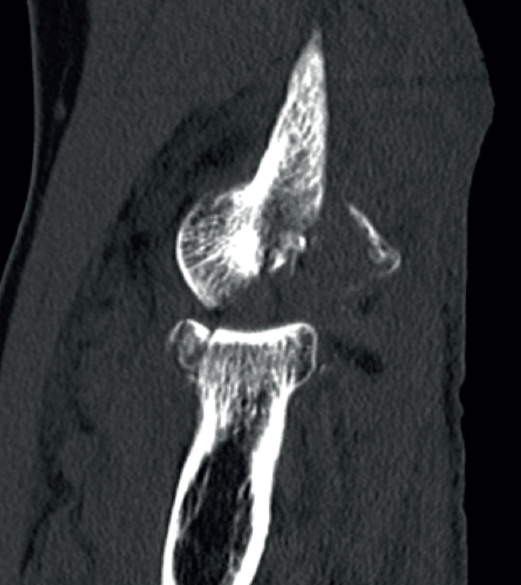

- Radiografía simple: puede orientarnos hacia una inestabilidad si se objetivan signos indirectos, tales como calcificaciones en la inserción ligamentosa, que sugieran antecedente de avulsión ligamentosa (Figura 7).

Signos de haber tenido fracturas en la cabeza del radio o la coronoides, aunque ya estén consolidadas, nos ponen en el contexto de un posible antecedente de luxación acompañando a las fracturas. También la presencia de fractura con fragmento cortical posterolateral del húmero, que ha sido considerado como el “Hill-Sachs del codo”(12)(Figura 8).

Y, por supuesto, signos directos, si objetivamos la articulación claramente subluxada (Figura 9).